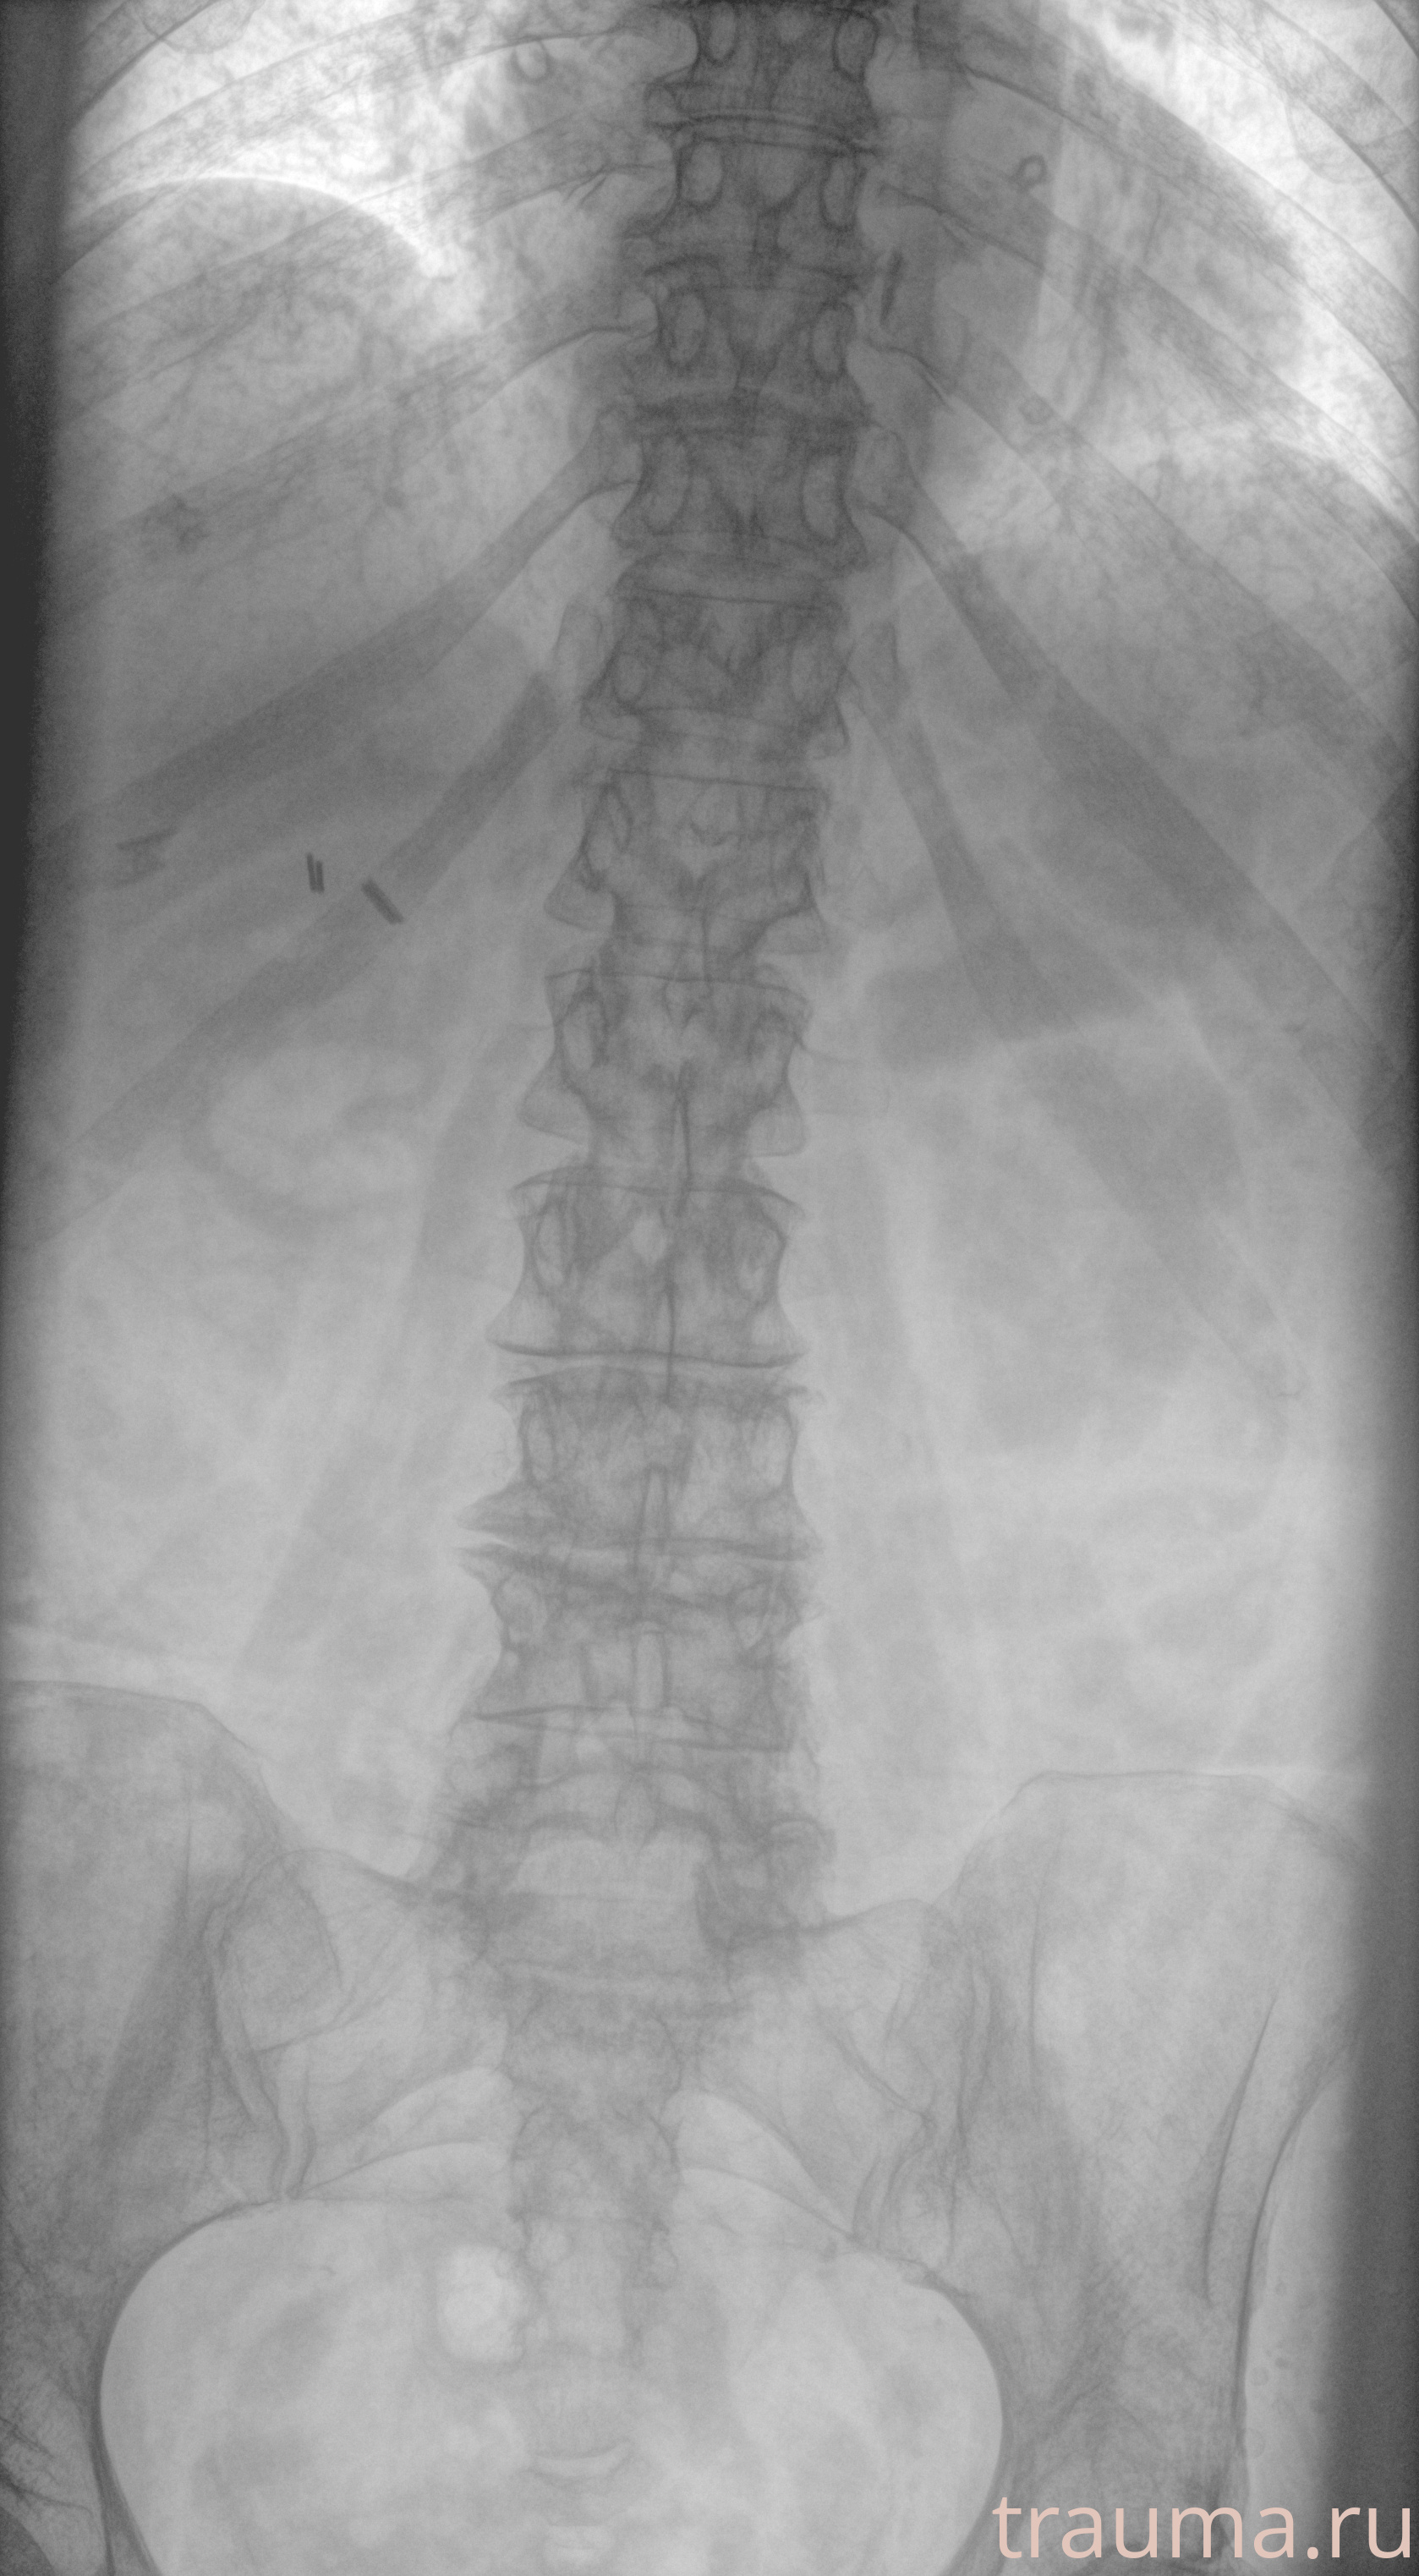

Рентгенограммы

Рентген на дому: по вашему адресу приезжает врач-рентгенолог, травматолог-ортопед с мобильным рентгеновским аппаратом, проводит диагностику травмы или заболевания, делает необходимые рентгенограммы, дает рекомендации по дальнейшему лечению. Получить качественные снимки в домашних условиях возможно благодаря уникальной методике, разработанной МосРентген Центром для института  Склифосовского